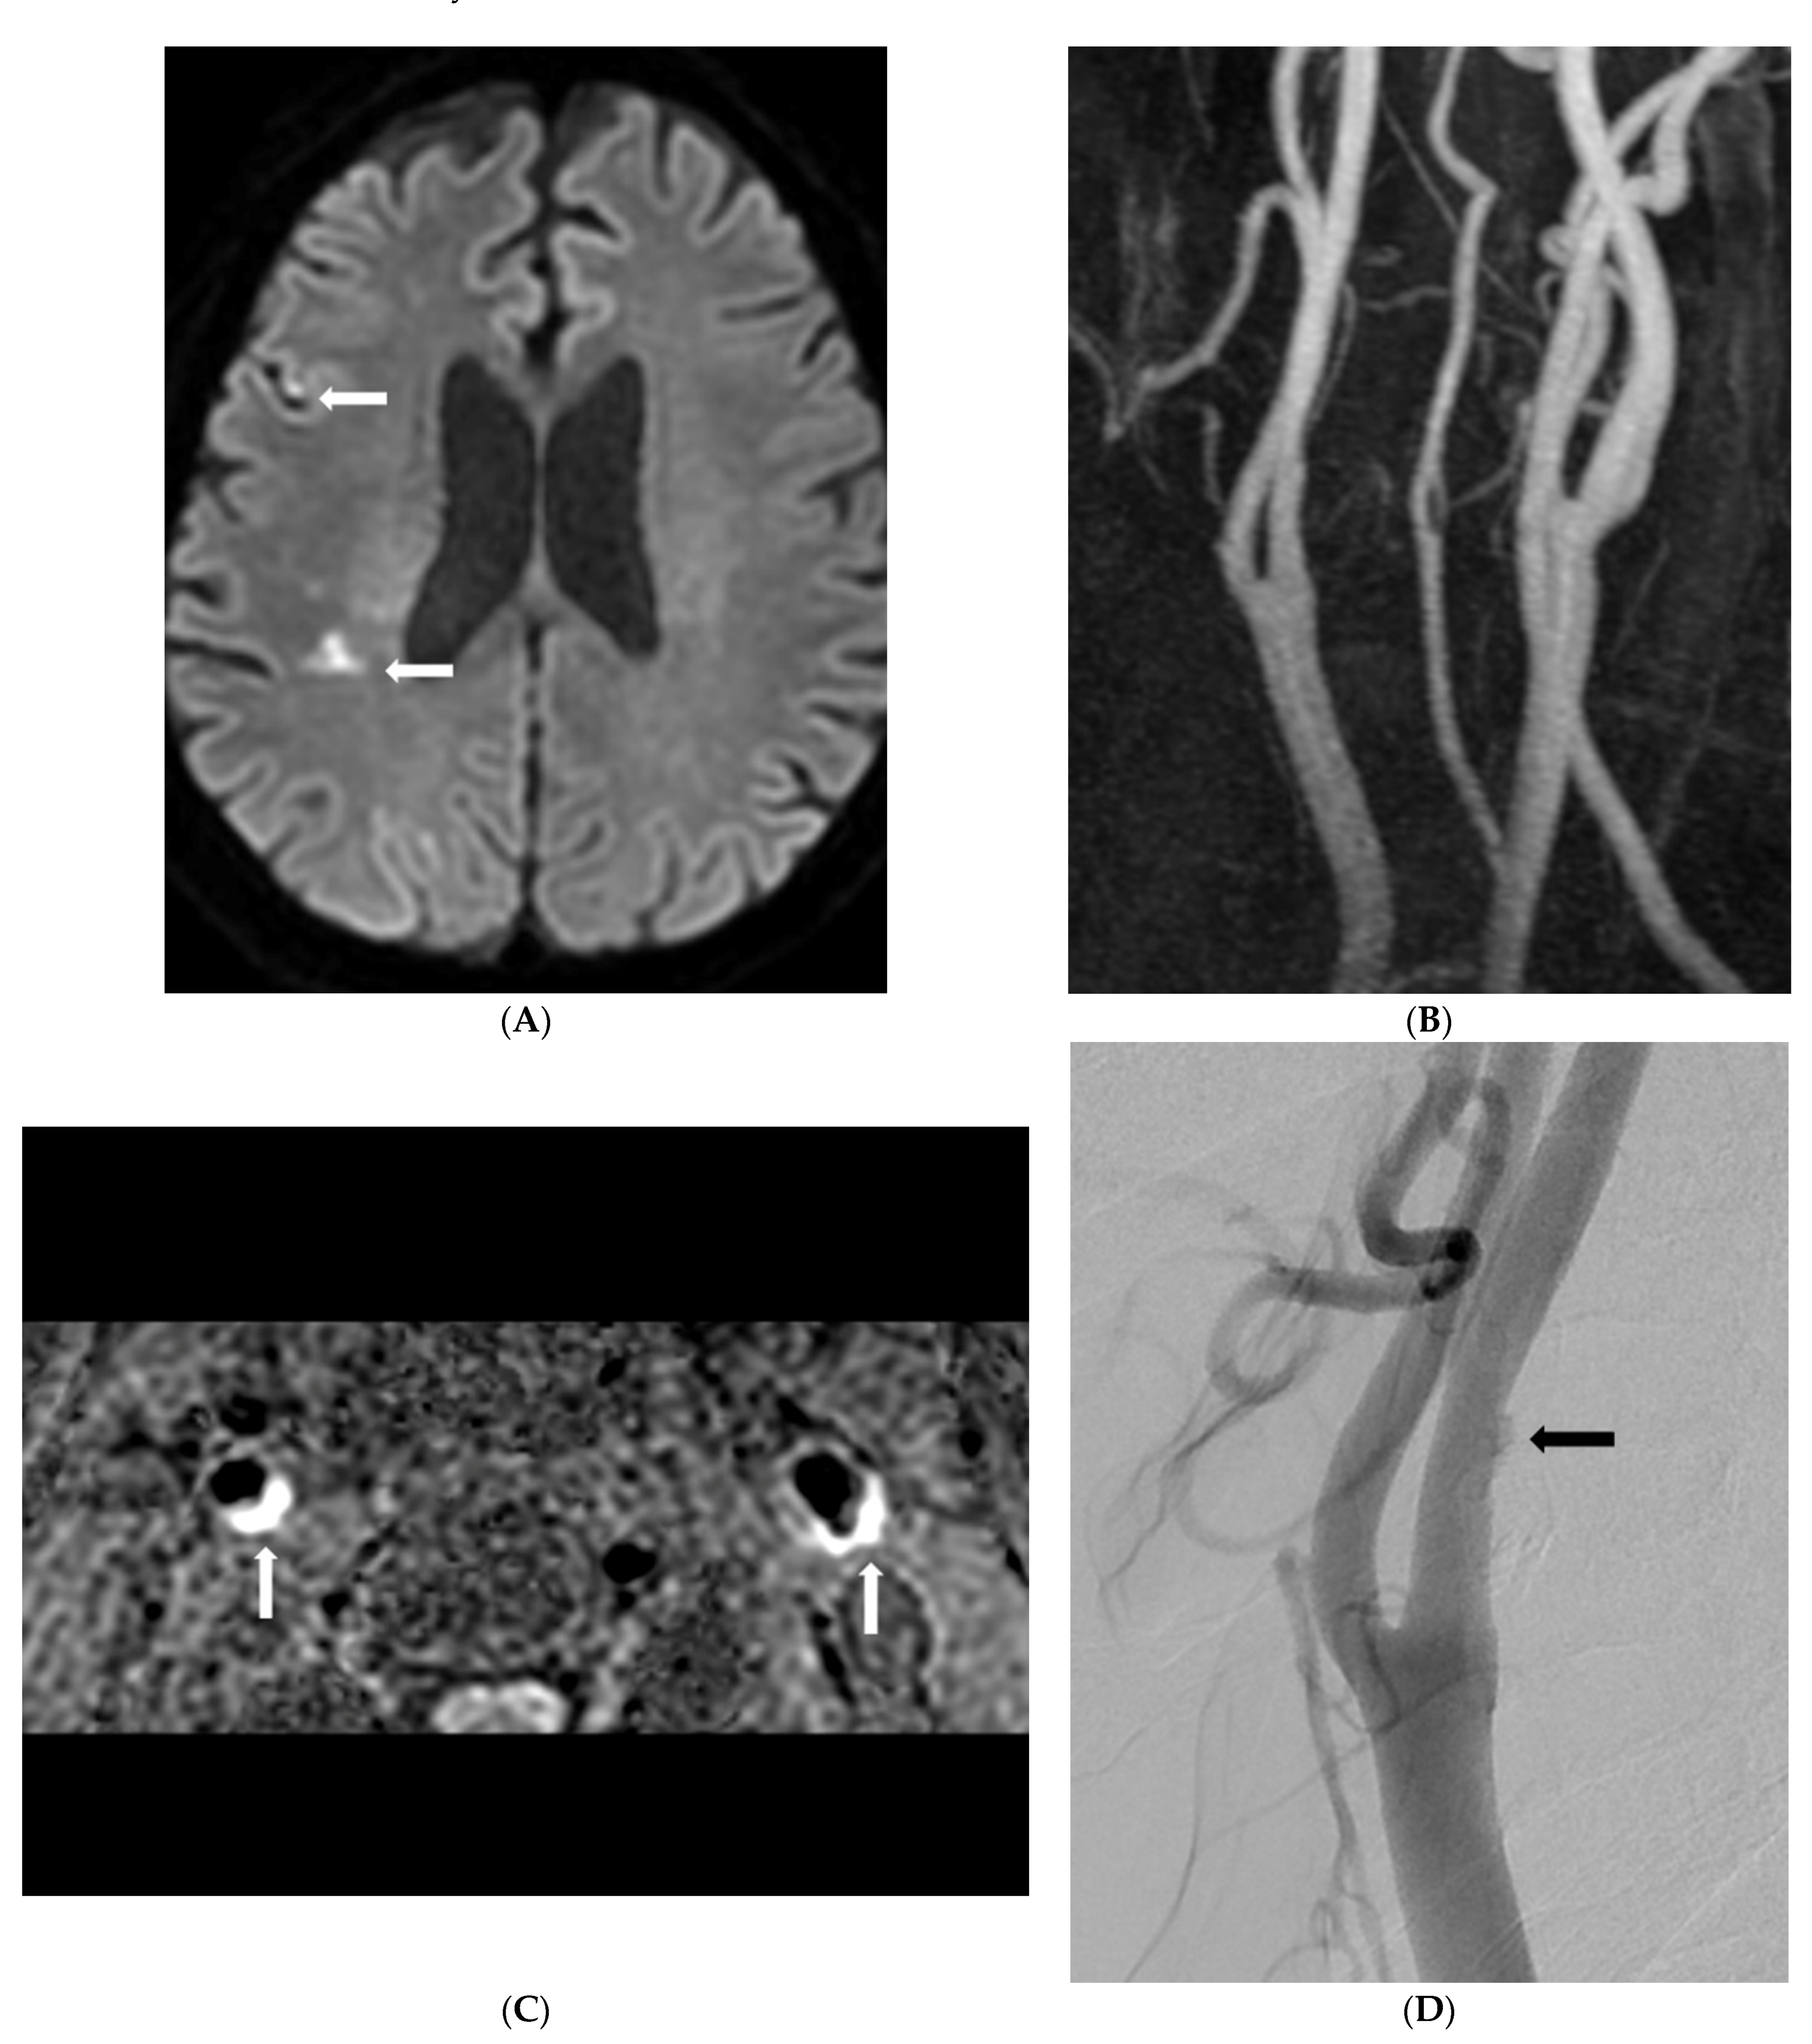

- Park, J.S.; Kwak, H.S.; Lee, J.M.; Koh, E.J.; Chung, G.H.; Hwang, S.B. Association of carotid intraplaque hemorrhage and territorial acute infarction in patients with acute neurological symptoms using carotid magnetization-prepared rapid acquisition with gradient-echo. J. Korean Neurosurg. Soc. 2015, 57, 94–99. [Google Scholar] [CrossRef]